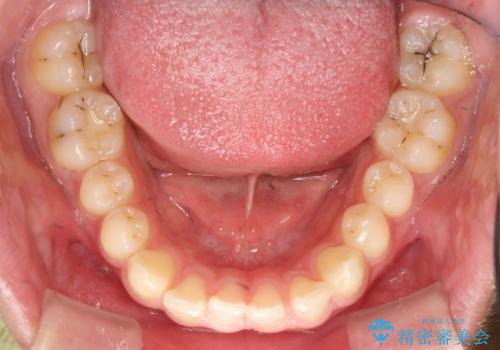

初診時の歯並びの状態としては、上下ともに前歯部の中等度のがたつきがあり、前歯には正中離開があり過蓋咬合を呈してい状態でした。

見た目、噛み合わせ及び、治療期間や施術内容に大変ご満足いただきました。